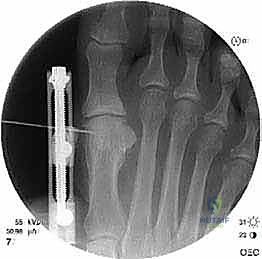

الخطوة الخامسة: التثبيت الداخلي القوي (Internal Fixation)

لضمان التئام العظم في وضعه الجديد والطويل، يجب تثبيته بقوة شديدة. يستخدم الدكتور هطيف أحدث الشرائح المعدنية التيتانيوم ذات الزاوية الثابتة (Locking Plates) والمسامير الدقيقة. هذا التثبيت القوي يمنع أي حركة بين العظام ويسمح ببدء العلاج الطبيعي في وقت مبكر.

الخطوة السادسة: الإغلاق التجميلي

بعد التأكد من الطول المثالي واستقرار التثبيت باستخدام الأشعة السينية في غرفة العمليات، يتم غسل الجرح بمضادات حيوية وإغلاق طبقات الأنسجة والجلد بخياطة تجميلية دقيقة لتقليل الندبات قدر الإمكان. يتم وضع ضمادة ضاغطة وداعمة للقدم.